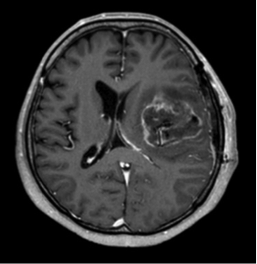

2.グリオーマ(神経膠腫)

脳そのものから発生する脳腫瘍の中で一番多い腫瘍です。悪性度の低いグレード1から、きわめて悪性のグレード4である膠芽腫まであります。なるべく手術で多く摘出しますが、場合によって診断をつけるだけの生検手術に終わる場合もあります。手術は顕微鏡、モニタリング、蛍光剤などを使って安全な手術を心がけています。放射線治療、化学療法も行います。

手術前